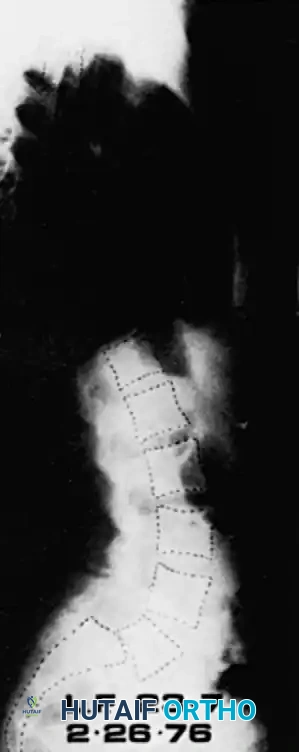

- Standing Lateral View: Mandatory for assessing the true degree of slippage. Lowe et al. demonstrated a 26% increase in measured slip on standing films compared to supine films.

Meyerding Classification:

The most universally applied system. The superior endplate of S1 is divided into four equal quarters. The grade is determined by the position of the posterior-inferior corner of L5 relative to S1.

* Grade I: < 25% slip

* Grade II: 25% - 50% slip

* Grade III: 50% - 75% slip

* Grade IV: > 75% slip

* Grade V (Spondyloptosis): L5 is completely displaced anterior and inferior to the sacral promontory.

DeWald Modification:

DeWald modified Newman's system to better quantify the anterior "roll" or kyphosis of L5. The sacral dome and anterior sacral surface are divided into 10 equal parts, providing a highly precise two-number score mapping both translation and angular displacement.

Boxall's Slip Angle:

Boxall et al. established that angular relationships (sagittal rotation or slip angle) are superior predictors of instability and progression compared to simple translational percentage. A high slip angle indicates severe localized lumbosacral kyphosis.